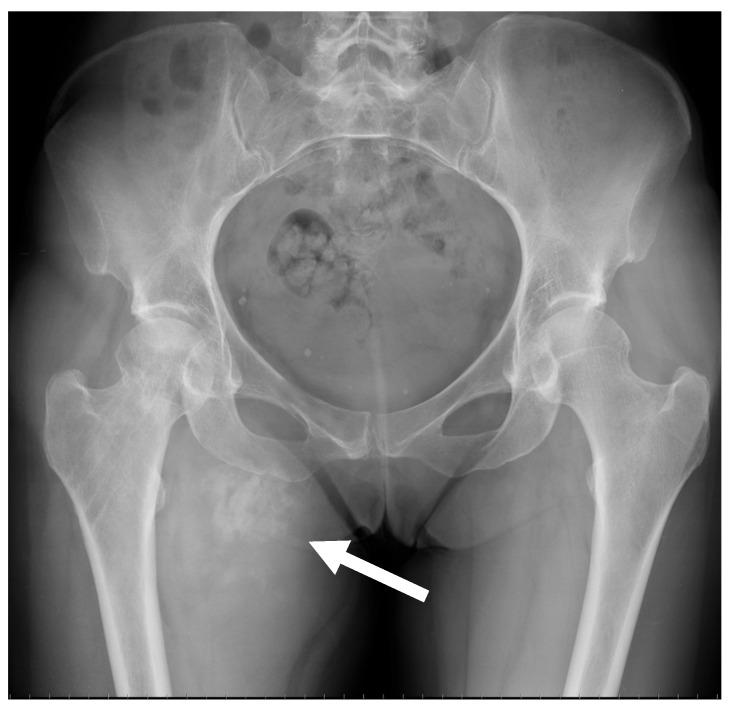

Osteosarcomas are rare malignancies (<1% of all cancers) that produce an osteoid matrix. Osteosarcomas are the second most frequent type of primary bone tumor after multiple myeloma and the most prevalent primary bone tumor in children. The spectrum of imaging findings of these malignancies varies significantly, reflecting different histological subtypes. For instance, conventional osteosarcoma typically presents with a mixed radiological pattern (lytic and bone mineralization) or with a completely eburneous one; aggressive periosteal reactions such as sunburst, Codman triangle, and soft-tissue components are frequently displayed. On the other hand, telangiectatic osteosarcoma usually presents as a purely lytic lesion with multiple fluid-fluid levels on MRI fluid-sensitive sequences. Other typical and atypical radiological patterns of presentation in other subtypes of osteosarcomas are described in this review. In addition to the characteristics associated with osteosarcoma subtyping, this review article also focuses on imaging features that have been associated with patient outcomes, namely response to chemotherapy and event-free and overall survivals. This includes simple semantic radiological features (such as tumor dimensions, anatomical location with difficulty of radical surgery, occurrence of pathological fractures, and presence of distant metastases), but also quantitative imaging parameters from diffusion-weighted imaging, dynamic contrast-enhanced MRI, and 18F-FDG positron emission tomography and radiomics approaches. Other particular features are described in the text. Overall, this comprehensive literature review aims to be a practical tool for oncologists, pathologists, surgeons, and radiologists involved in these patients' care.

骨肉瘤是一种罕见的恶性肿瘤(占所有癌症的比例不到1%),可产生类骨质基质。骨肉瘤是继多发性骨髓瘤之后第二常见的原发性骨肿瘤类型,也是儿童中最常见的原发性骨肿瘤。这些恶性肿瘤的影像学表现谱差异很大,反映了不同的组织学亚型。例如,传统骨肉瘤通常表现为混合性放射学模式(溶骨性和骨矿化)或完全骨化模式;常显示侵袭性骨膜反应,如日光放射状、科德曼三角和软组织成分。另一方面,毛细血管扩张性骨肉瘤通常表现为纯溶骨性病变,在MRI液体敏感序列上有多个液-液平面。本文综述了骨肉瘤其他亚型的其他典型和非典型放射学表现模式。除了与骨肉瘤亚型相关的特征外,本文还重点关注与患者预后相关的影像学特征,即对化疗的反应、无事件生存期和总生存期。这包括简单的语义放射学特征(如肿瘤大小、根治性手术困难的解剖位置、病理性骨折的发生以及远处转移的存在),也包括扩散加权成像、动态对比增强MRI、18F-FDG正电子发射断层扫描和放射组学方法的定量成像参数。文中还描述了其他特殊特征。总体而言,这篇全面的文献综述旨在成为参与这些患者护理的肿瘤学家、病理学家、外科医生和放射科医生的实用工具。